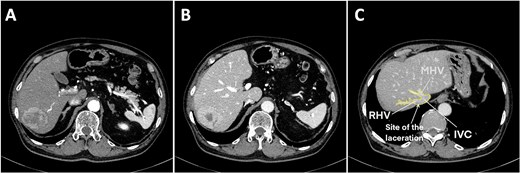

Under general anesthesia in the left lateral position, three 12-mm and three 5-mm trocars were inserted into the abdomen. The right liver was mobilized by dividing the round, right coronary, and triangular ligaments, and the inferior right hepatic veins (IRHVs) and dissection around the right hepatic vein (RHV) and IVC. Parenchymal transection was performed with intermittent Pringle maneuvers. Massive bleeding suddenly occurred from the dorsal RHV near the RHV root (Figs 1C and 2A) during transection, likely extending to the anterior RHIVC (Fig. 2B). This bleeding may have been caused by excessive traction on the liver during transection. Laparoscopic hemostasis failed and the patient developed hemorrhagic shock with the systolic blood pressure dropping to 30 mmHg. Hakuzo Sterile OP Gauze NEO (2.5 × 10 cm and 4-ply; Osaka, Japan; Fig. 3D) was used to control bleeding.

Laceration of the IVC. (A) Right liver mobilization and hanging of the RHV by laparoscopy with the laceration site marked where the small, short hepatic vein was electrocauterized. (B) Hemorrhage from the IVC injury during laparoscopic surgery. (C ) The initial laceration on the IVC was ~1 cm in size and during gauze packing a small gauze migrated into the IVC through the laceration. (D) The IVC laceration extended to the root of the RHV. The laceration was ~5 cm in length and occupied one-half of the IVC circumference. (E) The laceration was closed with two sutures at the beginning and end of the laceration. (F) Hemorrhage was minimized with finger pressure. (G) The IVC laceration was repaired with continuous sutures using 4.0 Prolene sutures. (H) The IVC injury was successfully repaired. (I) Postoperative computed tomography image showing a reduction in the IVC diameter at the hepatic vein junction by approximately one-half. Abbreviations: IVC, inferior vena cava; RHV, right hepatic vein; IRHV, inferior right hepatic vein; S7, segment 7; S8, segment 8.

Emergency conversion to open surgery was performed. A 0.5-cm laceration (Fig. 2C) in the anterior RHIVC had extended to a nearly 5-cm tear involving the RHV root and nearly one-half of the IVC circumference (Fig. 2D). The extended laceration was likely caused by excessive compression applied during hemostasis with residual hepatic attachment to the IVC, under which even minimal traction exacerbated the tear. Hemorrhage was initially controlled by manual compression and two anchoring Prolene sutures at both ends of the laceration (Fig. 2E). Given the low central venous pressure (~5 cmH₂O), partial closure using two anchoring sutures and manual pressure (Fig. 2F) significantly reduced the bleeding. Hemostasis was achieved with continuous 4-0 sutures (Fig. 2G). The repaired RHIVC diameter was reduced by one-half (Fig. 2H and I). Hemodynamic stability was assured and the liver transection was completed. The total blood loss was 7729 ml, the intraoperative blood transfusion volume was 3640 ml, and the operative time was 535 minutes. The gauze count revealed one missing laparoscopic gauze. Despite thorough reinspection and intraoperative chest and abdominal X-rays, the gauze was not found. Given the patient’s unstable condition, the operation was concluded and the patient was transferred to the intensive care unit.